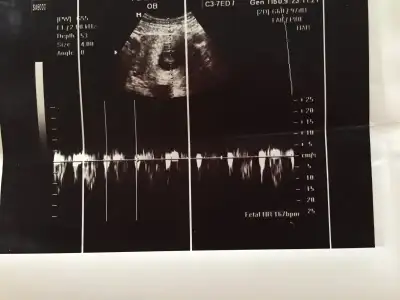

Ultrason Karından mı yoksa vajinal mi canım?Biri 7 haftalik ikincisi 9 haftaya yakin olan resmi

7 haftalik olan vajinal canim digeri karindanUltrason Karından mı yoksa vajinal mi canım?